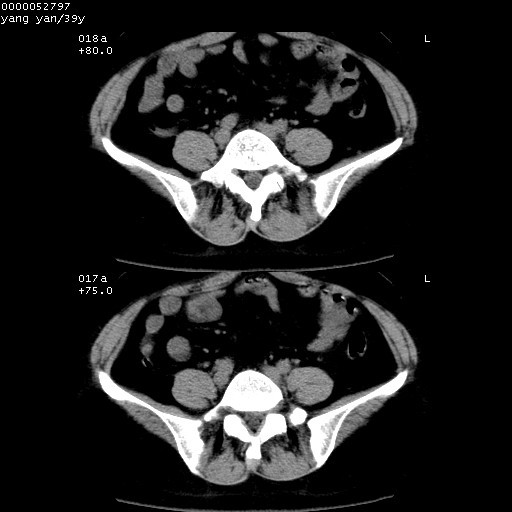

患者 女,39岁。因外伤检查,偶然发现。

典型!双侧骶髂关节致密性骨炎。

典型!病变主要累及双侧髂骨。常见于育龄期妇女。

致密性骨炎,一般不跨越关节面,可是这个骶骨关节面也有硬化。

髂骨致密性骨炎系一种以骨质硬化为特点的非特异性炎症,有高度致密的骨硬化现象,尤其以髂骨下2/3更为明显,但关节间隙则无改变。因位于骶髂关节,且该关节症状明显,故又称之为“骶髂关节致密性骨炎”。 本病90%以上为中年女性,以妊娠后期、尤其分娩后为多见,亦可见于尿路或女性附件慢性感染后,或盆腔内其他感染。此外,臀骶部的外伤亦可诱发或引起本病。  妊娠、分娩及外伤均可引起骶髂关节韧带的撕裂而易使局部的血供受阻。因此早期局部呈现充血、水肿及渗出增加等,渐而局部出现增生与变性反应,随着胶原纤维的致密化而向硬化演变;血管形成厚壁血管,易闭塞而引起髂骨耳状面处缺血和缺氧,骨质呈现硬化性改变,以致手术时局部出血较少。骶髂关节囊壁显示纤维增生、弹性降低及松动样改变。继发于盆腔内炎症者亦出现相类似的病理改变,可能系细菌内毒素作用所致。